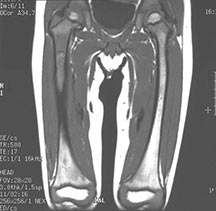

Sites:

- Flat Bones (most common—70%)

- Skull

- Pelvis

- Femur

- Humerus